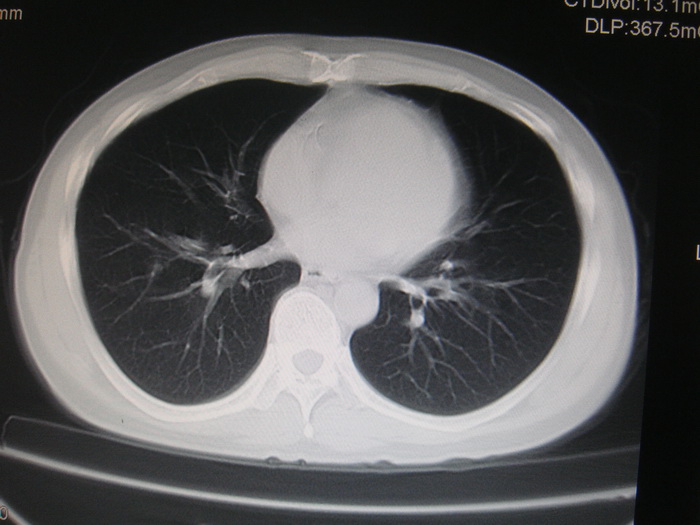

标题: CT28366:男性,45岁,偶尔发现右颈部肿块行胸部CT扫描。 [打印本页]

男性,45岁,偶尔发现右颈部肿块行胸部ct扫描。

两肺多发结节灶及纵膈淋巴结肿大考虑为转移

两肺多发性转移瘤,纵隔淋巴结转移。

两肺多发性转移瘤,纵隔淋巴结转移。食道中上段管壁似乎增厚,作相关检查。

两肺多发性转移瘤,前上纵隔淋巴结转移。